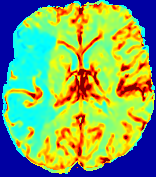

Slice #1Slice #2Slice #3Slice #4Slice #5Slice #6Dgtsuperscript𝐷gtD^{\text{gt}}Refer to captionRefer to captionRefer to captionRefer to captionRefer to captionRefer to captionDestsuperscript𝐷estD^{\text{est}}Refer to captionRefer to captionRefer to captionRefer to captionRefer to captionRefer to captionRefer to caption0.300.300.300.240.240.240.180.180.180.120.120.120.060.060.060.000.000.00(mm2/s)𝑚superscript𝑚2𝑠(mm^{2}/s)𝐕est𝟐subscriptnormsuperscript𝐕est2\|\bf{V}^{\text{est}}\|_{2}Refer to captionRefer to captionRefer to captionRefer to captionRefer to captionRefer to captionRefer to caption0.00300.00300.00300.00240.00240.00240.00180.00180.00180.00120.00120.00120.00060.00060.00060.00000.00000.0000(mm/s)𝑚𝑚𝑠(mm/s)

Figure 15: PIANO identifiability testing: diffusion imaging via advection-diffusion. Top row shows Dgtsuperscript𝐷gtD^{\text{gt}} used for simulating ground truth pure diffusion. Rows below show the estimated Destsuperscript𝐷estD^{\text{est}} and 𝐕est2subscriptnormsuperscript𝐕est2\|{\bf{V}}^{\text{est}}\|_{2} on corresponding slices. Note that the plotted value scale for 𝐕est2subscriptnormsuperscript𝐕est2\|{\bf{V}}^{\text{est}}\|_{2} is 0.01 of that for Dgtsuperscript𝐷gtD^{\text{gt}} and Destsuperscript𝐷estD^{\text{est}}.

Similarly, we test the behavior of PIANO when estimating both advection and diffusion from a pure diffusion-driven process. The goal is to determine if PIANO is able to recognize that there is only diffusion governing the given concentration time-series. We use the same ‘Diffusion Imaging’ data simulation of Sec. 4.2.1 as the concentration dataset, PIANO estimates both velocity 𝐕estsuperscript𝐕est{\bf{V}}^{\text{est}} and diffusivity Destsuperscript𝐷estD^{\text{est}}. Estimation results in Fig. 15 confirm PIANO’s identifiability again: the estimated 𝐕est2subscriptnormsuperscript𝐕est2\|{\bf{V}}^{\text{est}}\|_{2} is almost invisible compared to Destsuperscript𝐷estD^{\text{est}}, even plotted with a 1%percent11\% value range compared to that for Destsuperscript𝐷estD^{\text{est}}. On the other hand, Destsuperscript𝐷estD^{\text{est}} achieves comparable estimation performance as ‘Diffusion Imaging via Diffusion’ in which PIANO predicts Destsuperscript𝐷estD^{\text{est}} alone (shown in Fig. 13).